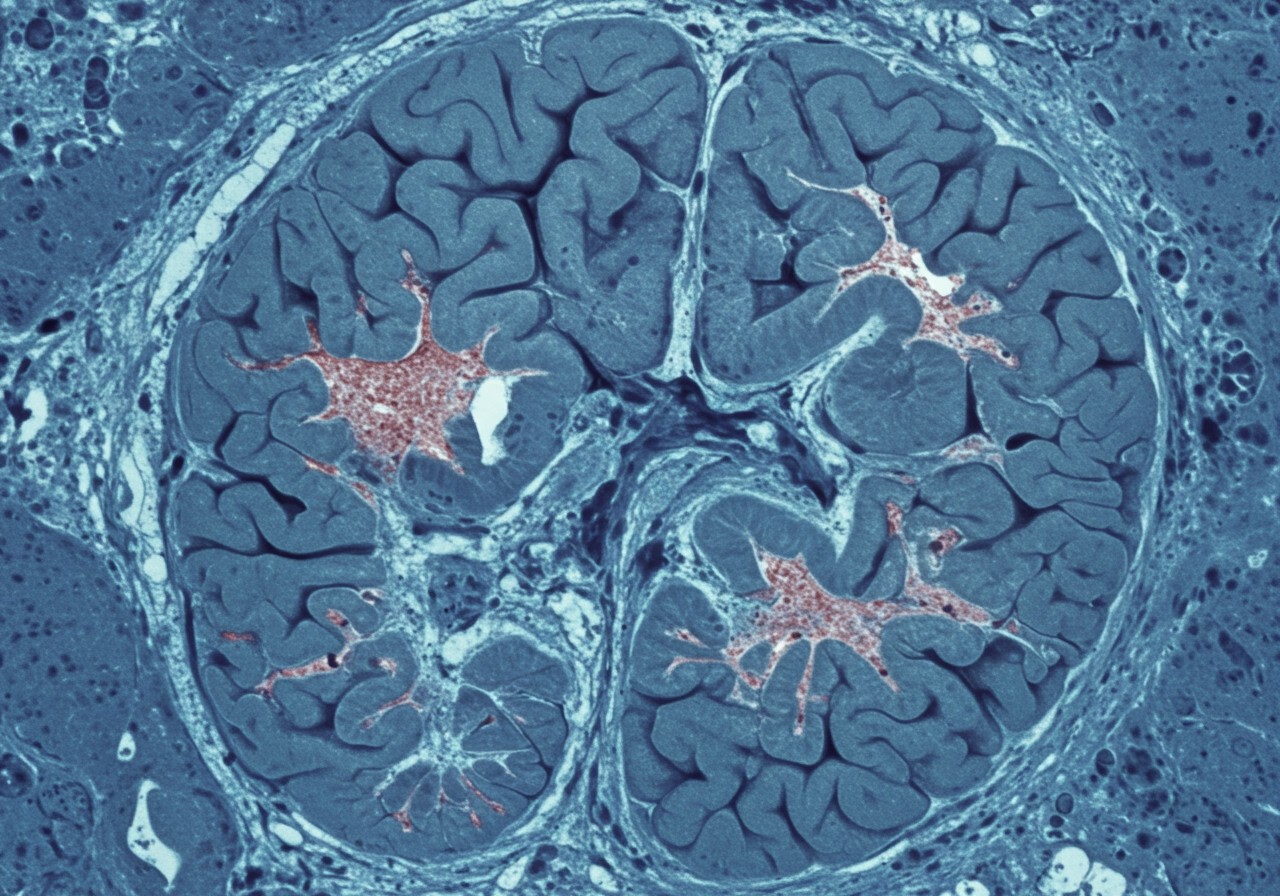

A kokain, kémiai nevén benzoilmetilekgonin, egy erőteljes stimuláns, amely a központi idegrendszerre gyakorolt hatásán keresztül fejti ki hatását. Molekuláris szerkezete lehetővé teszi, hogy könnyen átjusson a vér-agy gáton, így gyorsan eléri az agyat.

A kokain elsődleges hatásmechanizmusa a dopamin, noradrenalin és szerotonin neurotranszmitterek visszavételének gátlása az idegsejtek szinaptikus résében. Ez azt jelenti, hogy ezek a neurotranszmitterek, amelyek a hangulat, a mozgás és a figyelem szabályozásában játszanak kulcsszerepet, hosszabb ideig maradnak jelen a szinapszisban, ami túlzott stimulációt okoz.

Különösen a dopamin szintjének növekedése felelős a kokain euforikus hatásaiért és addiktív potenciáljáért. A megnövekedett dopamin-szint aktiválja az agy jutalmazási rendszerét, ami megerősíti a drogkereső viselkedést. A kokain hatása a noradrenalinra növeli a pulzusszámot, a vérnyomást és a testhőmérsékletet, ami szív- és érrendszeri problémákhoz vezethet. A szerotoninra gyakorolt hatása pedig hozzájárulhat a hangulatzavarokhoz és a szorongáshoz.

A kokain által kiváltott központi idegrendszeri stimuláció közvetlen és közvetett módon is befolyásolhatja a szemet. A közvetlen hatások közé tartozik a pupillák kitágulása (midriázis), ami a szem fokozott fényérzékenységéhez vezethet. A közvetett hatások pedig, mint például a megemelkedett vérnyomás és a szívritmuszavarok, károsíthatják a szem ereit, ami látásvesztéshez vezethet.

A központi idegrendszerre gyakorolt ezen komplex hatások elengedhetetlenek a kokain szemkárosító potenciáljának megértéséhez, mivel a megnövekedett vérnyomás és a neurotranszmitter egyensúlyának felborulása közvetlenül befolyásolhatja a szem vérellátását és idegi funkcióit.

A kokain által kiváltott idegrendszeri stimuláció továbbá szemtekerezgéshez (nisztagmus) is vezethet, ami akaratlan, gyors szemmozgásokat jelent. Ez a jelenség a kokain hatására az agytörzsben található egyensúlyközpontok zavarából adódik.